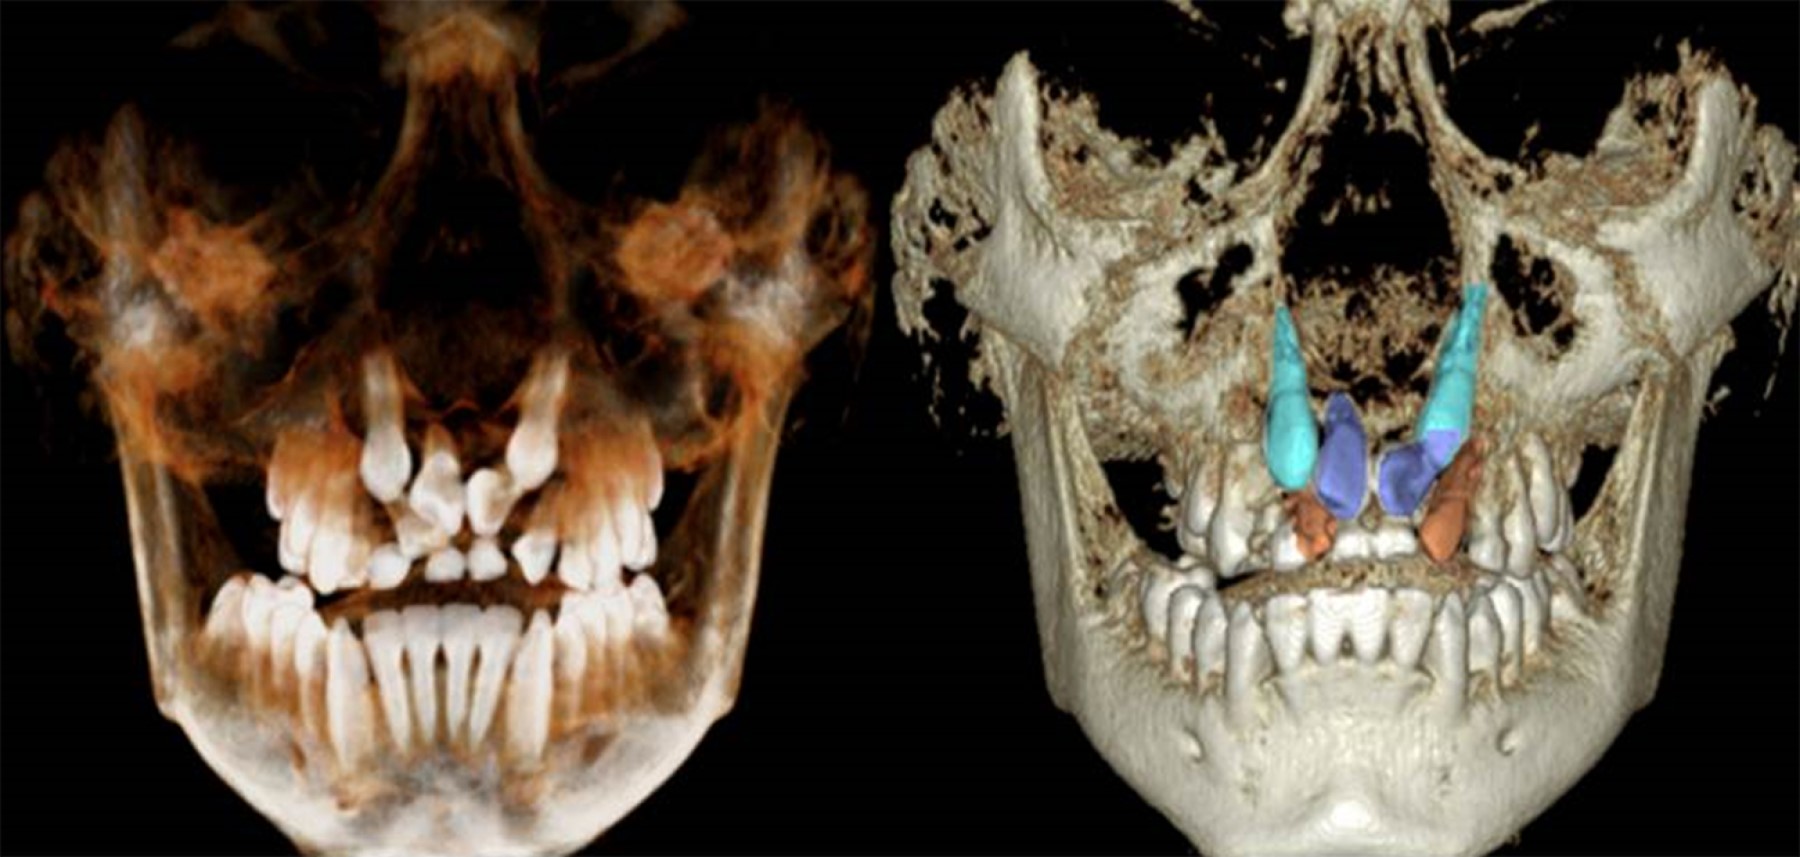

Initial cone beam computed tomography (Figure 4). showed bilateral incomplete transposition. In blue the upper central incisors, in light blue the upper canine teeth transposed, and in orange the upper lateral incisors.